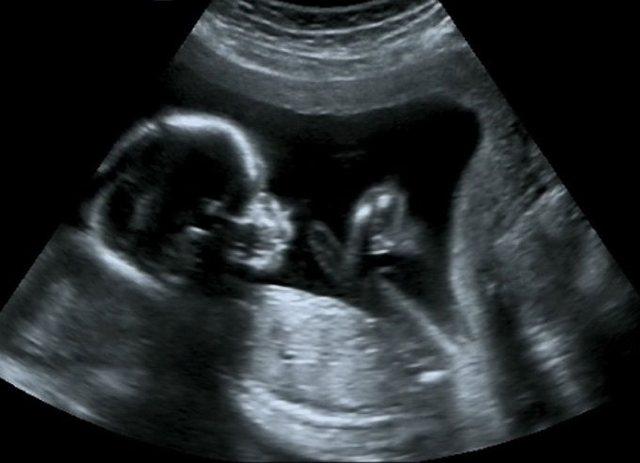

四维彩超表面成像用于产科检查,不仅可观察到胎儿成长的过程,而且能够直观地看到胎儿在母体内的活动状况,如:呼吸情况,运动情况,包括整个身体大的运动,肢体的运动,甚至是胎儿细小的吞咽动作等。医生还可以通过四维彩超来观察胎儿的张力是否良好。

在做四维检查的时候,是能够清晰看到宝宝的性别的,因为这个时间异性宝宝的性器官已经开始发育了,男宝宝和女宝宝是有明显区别的。另外,四维检查也能够清晰看到宝宝的面部轮廓,很多妈妈都说宝宝出生时候的样子和四维检查时候的样子是比较像的。